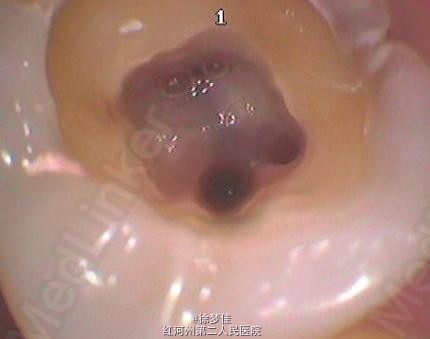

左下6近中根管断针X-P,断针长度约4MM, 根尖慢性炎症

插针确定断针根管,为近舌根管,插针有阻力,EDTA封存一周复诊。打开根管上部通路,根管大量清洗剂等冲洗,找到后,直接用超声根管搓15号带出断针。